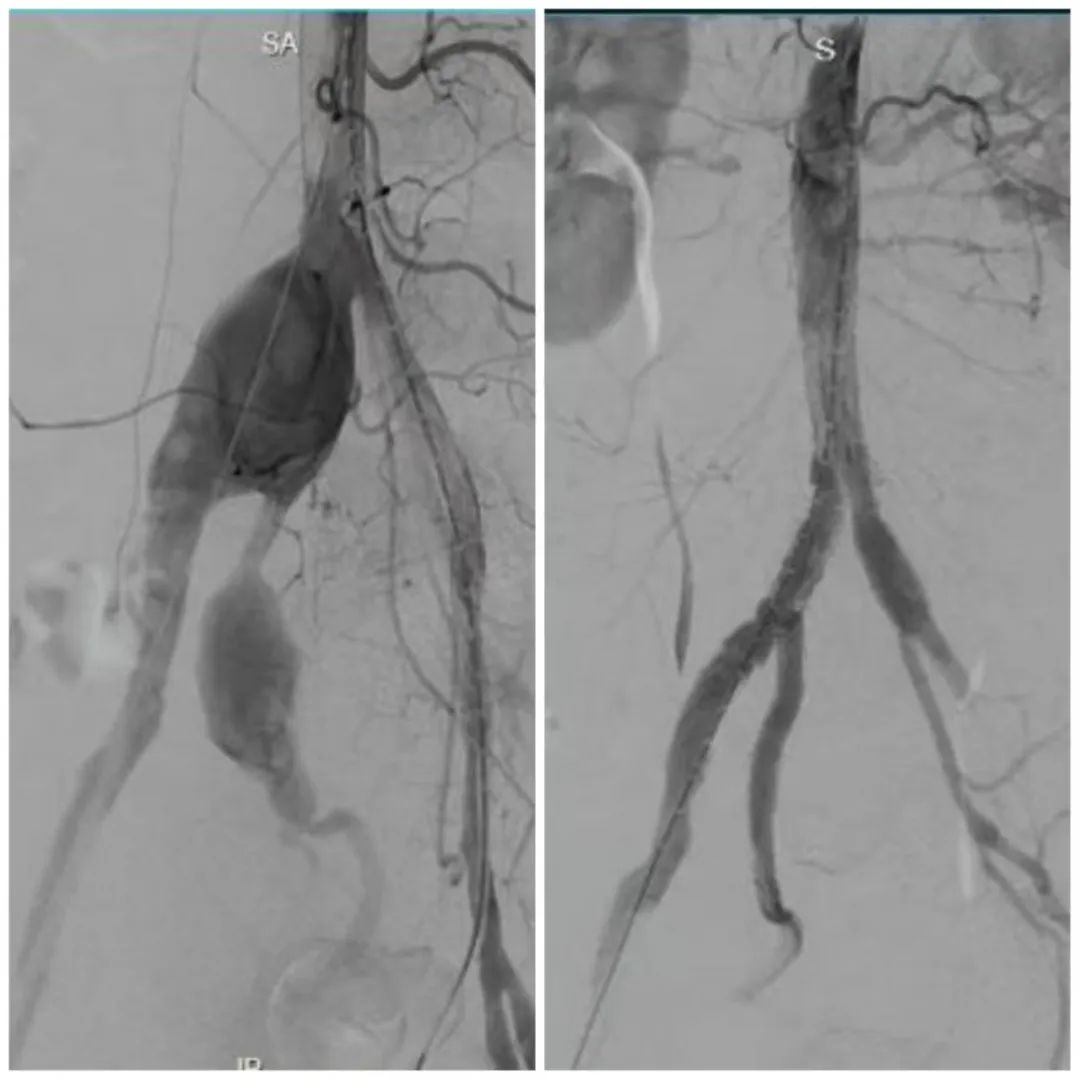

无需大动干戈,也能像“血管绣花”般精准修复病变,让患者术后回归正常生活。近日,37岁的汪先生(化名)突发持续性腰背胀痛,CT(电子计算机断层扫描)检查发现右侧髂总动脉瘤累及腹主动脉下端、右侧髂内动脉瘤,同时还伴有右侧髂外动脉夹层动脉瘤形成,这意味着其体内存在多处随时可能破裂的“血管炸弹”,一旦血管破裂将危及生命。然而,由于汪先生合并特殊感染,病情复杂,辗转多家医院均未能得到及时有效治疗。

“传统的开放性人工血管置换手术创伤巨大,并发症多。”上海市公共卫生临床中心介入科周粟主任团队接诊后,决定采用微创的腹主动脉腔内修复术(EVAR)搭配髂动脉分支支架(IBD)技术精准“拆弹”。

在时长2小时的手术中,团队精准释放髂动脉分支支架与腹主动脉覆膜支架,在隔绝髂总、髂内动脉瘤及髂外动脉夹层的同时,成功将分支支架延伸入右侧髂内动脉远端分支,保障重要血流不中断。术后次日汪先生就能下床活动,并在不久后康复出院。

复查显示,支架位置精准,瘤体和夹层被有效隔绝,髂内动脉血流通畅无渗漏。手术不但为汪先生消除了致命风险,而且从根源上预防了因髂内动脉闭塞导致的臀部缺血性疼痛、跛行、坏死以及性功能障碍等问题。